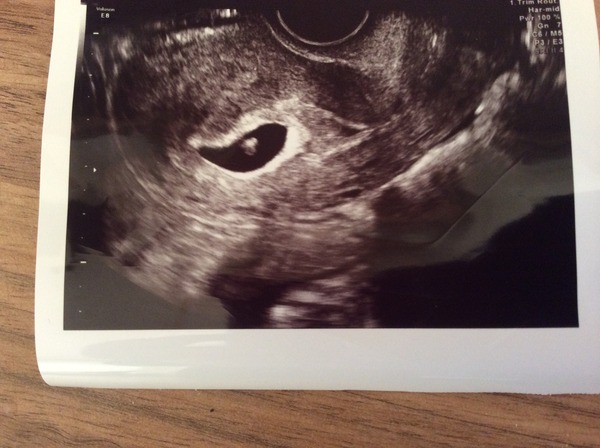

alien11 · 10/02/2015 21:07

batfish 5+6 scan photo x

That pic is amazing alien!

I can't believe you can see that already alien that's incredible.

Alien you must so be relieved, nothing as exciting as hearing the heartbeat and seems my the little flicker, congratulations! We haven't thought about names yet, though we have a long list from the one that was unsuccessful.

Alien thats amazing. I'm a week futher along and can't really imagine that there is anything in there!